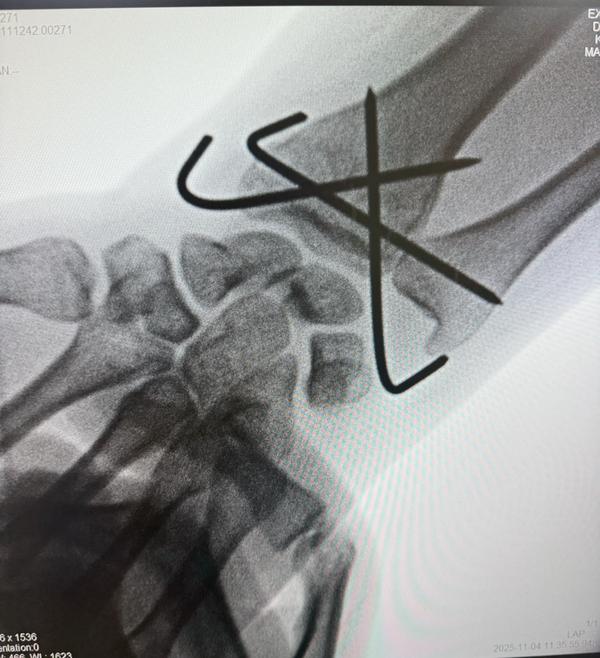

Distal end radius fracture of young patient operated with Closed reduction and K wire fixation